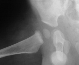

- Hospital Day 6: Respiked to 103.4. R hip Xray showed a defect in proximal

medial metaphysis, Possible osteomyelitis. The child was than taken to

the operating room for Incision & Drainage of Right hip via anterolateral

approach with suction irrigation system (seropurulent fluid drained).

- Post Operative Day 7: Drains removed. Respiked to 101.6. R hip Xray:

suggestion of demineralization of proximal metaphysis. The hip was reaspirated

and pus was obtained. Cultures neg.